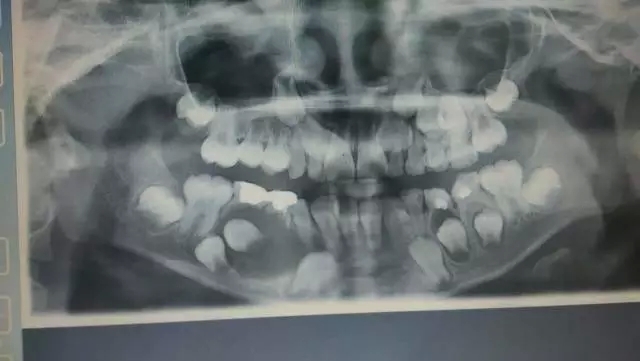

经全景片检查示:右侧下颌骨体部可见一类圆型单囊透射阴影,含44恒牙牙胚,颌骨边缘光滑,边界清晰,囊壁累及乳牙及45恒牙,邻界右下牙槽神经血管,诊断为“右下颌骨囊肿(含牙囊肿)”。

全景片示:右下颌巨大颌骨囊肿,邻界右下颌神经血管